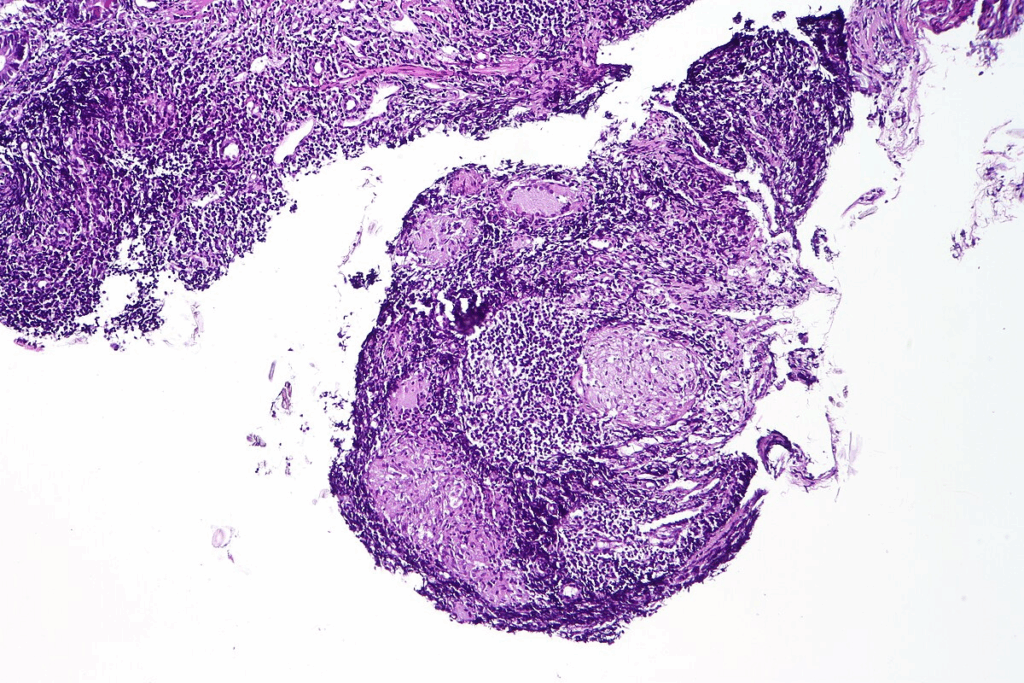

Chronic mucocutaneous candidiasis is a key sign of APECED. It’s an autoimmune condition that affects the skin and mucous membranes. People with this condition often get fungal infections, like thrush, in their mouths.

Oral Candidiasis as the Initial Manifestation

Oral candidiasis is usually the first sign of APECED. It shows up as white patches on the tongue and cheeks. These patches can be red and sore.